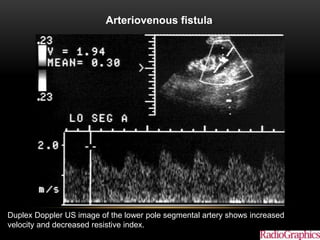

Arteriovenous fistula.

Color Doppler US image demonstrates a highly vascular lesion.

Duplex Doppler US image of the lower pole segmental artery shows increased

velocity and decreased resistive index.

Arteriovenous fistula. Akbar SA et al. Radiographics 2005;25:1335-1356 ©2005 by Radiological Society of North America Duplex Doppler US image of the lower pole segmental artery shows increased velocity and decreased resistive index.